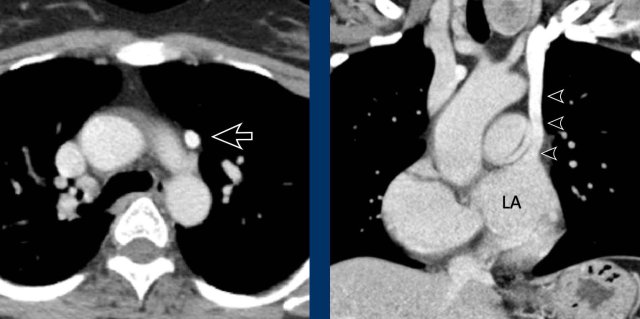

Bronchial artery hypertrophy can be seen for example in severe parenchymal disease and chronic thrombo-embolic pulmonary hypertension.

Images

Hypertrophy of the bronchial artery up to 4 mm in diameter (arrows) with a small aneurysm (arrowhead).